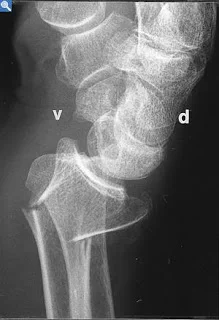

Monteggia Fracture/Dislocation

- Fracture of the proximal third of the ulna with dislocation of the head of the radius

- Dislocated head of radius missed if two joints are not included on the x-ray

- “Fracture of necessity”. Treated by:

- Open reduction and internal fixation of ulna

- Closed reduction of head of radius

- +/- fixation